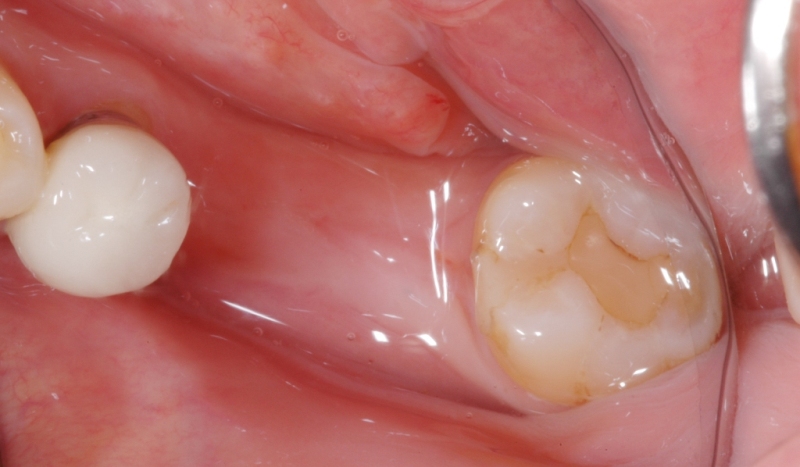

牙肉重建術案例

案例2

牙肉重建術前

牙肉重建術後